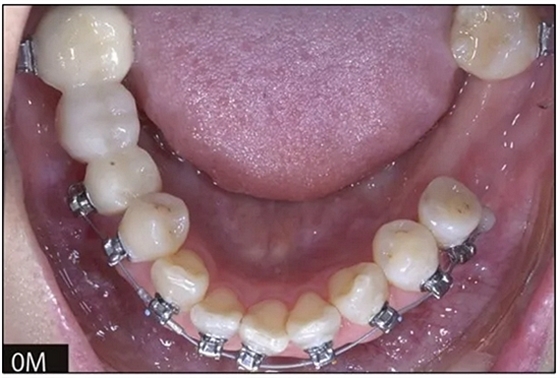

36歲;女性;尋求下頜左后方區(qū)域間隙管理的建議(圖1和圖2),通過治療獲得了良好的牙頜面效果(圖3和圖4)。她被診斷患有骨性I類和代償性牙性II類錯合畸形,并且上頜左側(cè)尖牙缺失(圖1和2)。大約七年前,由于不可修復(fù)的齲齒,拔除了下頜左側(cè)第一和第二磨牙(圖5)。37相鄰的第三磨牙向近中移動并傾斜入間隙,導(dǎo)致無牙頜間隙減小至約14 mm(圖2和圖5)。臨床和影像學(xué)評估顯示多發(fā)性齲損和在下頜右側(cè)567處有一不良的固定橋修復(fù)體(圖1和5)。此外,下頜左中切牙缺失,造成下頜中線向左側(cè)偏移約3 mm(圖1和圖2)。患者自訴,她的右上第一前磨牙和左上尖牙在13歲時由其家庭牙醫(yī)拔除,因?yàn)樗鼈儽蛔枞筋a側(cè)萌出(圖1)。上頜第二磨牙缺失(未知病因),并且相鄰的第三磨牙已經(jīng)轉(zhuǎn)移到第二磨牙間隙中。如補(bǔ)充材料所示,美國正畸學(xué)差異指數(shù)DI是28分。種植體部位(下頜左側(cè)和右側(cè)第一磨牙)由于復(fù)雜性得到額外4分(補(bǔ)充材料)。

圖2. 治療前牙齒模型